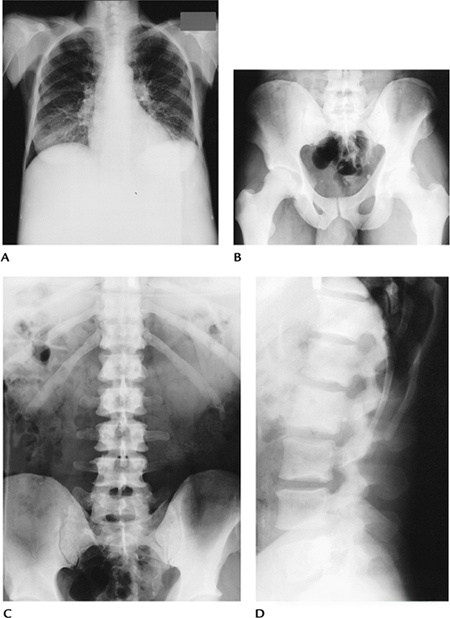

a8b6860d311652176283f3b390b744ca.png

图-8嗜酸性肉芽肿。(A)股骨的前后位X光片显示一个溶骨性病变,伴有骨内膜扇贝样侵蚀和骨膜反应。脊柱的前后位(B)和侧位(C)X光片显示T6椎体明显的压缩(扁平椎)。